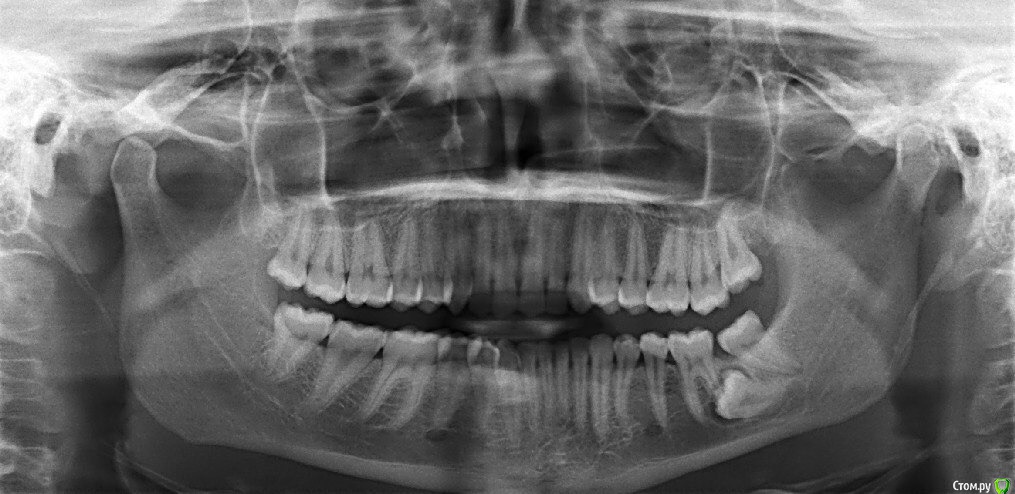

katya_bond Опубликовано 13 октября, 2017 Автор Поделиться Опубликовано 13 октября, 2017 Беспокоило расстояние между зубами, из-за которого приём пищи причиняешь дискомфорт. Записалась на консультацию к ортодонту, попросили прийти со снимком. На снимке видно, что там не просто расстояние, а зуб. Существует ли какой-то вариант, при котором можно избежать удаления данного зуба? Ссылка на комментарий

katya_bond Опубликовано 13 октября, 2017 Автор Поделиться Опубликовано 13 октября, 2017 Про какой зуб вопрос? Который крайний или который не вырос там где надо?Который не вырос там где надо Ссылка на комментарий